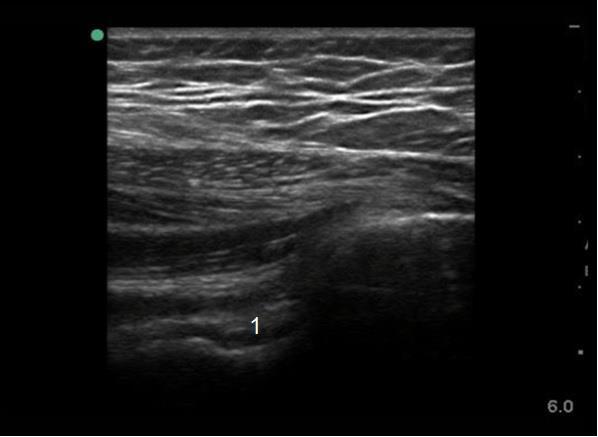

Imagen 1 del cuello del fémur en el lateral de la cadera

Cuello del fémur